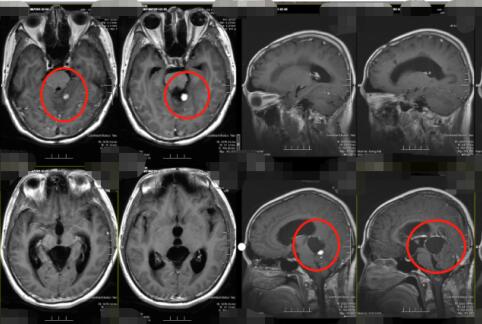

▲术前